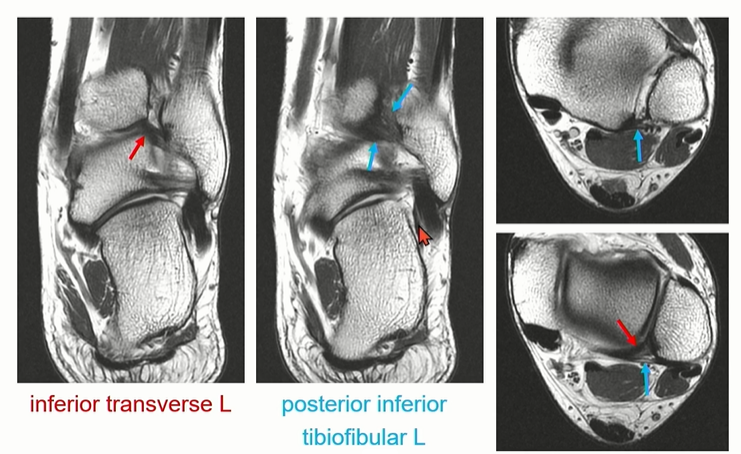

PITFL 은 superfical component와 deep component로 구성된다.

deep component를 inferior transverse ligament라고 부름. 이름대로 horizontal 하게 주행하는 것을 확인할 수 있다.

PITFL은 superficial 과 Deep으로 나누어 보기도 한다.

빨간색으로 표시된 inferior transverse ligament가 아래 쪽에서 주행하는 것을 확인할 수 있다.

파란색으로 표시한 posterior inferior tibiofibular ligment는 위쪽에서 oblique하게 주행하는 것을 확인할 수 있다.